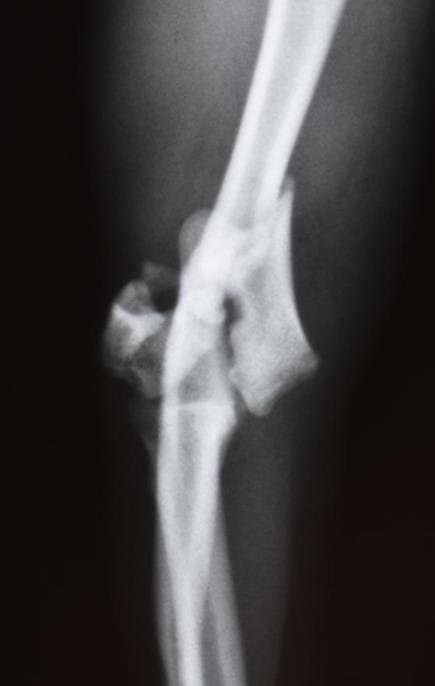

무릎뼈 확인

먼저 발이 닿지 않는 의자에 앉은 후 무릎뼈를 꾸욱 눌러보시길 바랍니다. 이때 무릎뼈와 다리 사이에 있는 연골의 있어 헷갈릴 수 있는 만큼 예민하게 살펴보시길 바랍니다.

만약 성장판이 닫힌 어른의 경우라면 말랑거리고 안으로 들어가지만 그렇지 않은 아이의 경우 조금 다른데요. 약간의 딱딱함이 느껴진다면 성장판이 아직까지 열려 있다고 생각하실 수 있습니다.